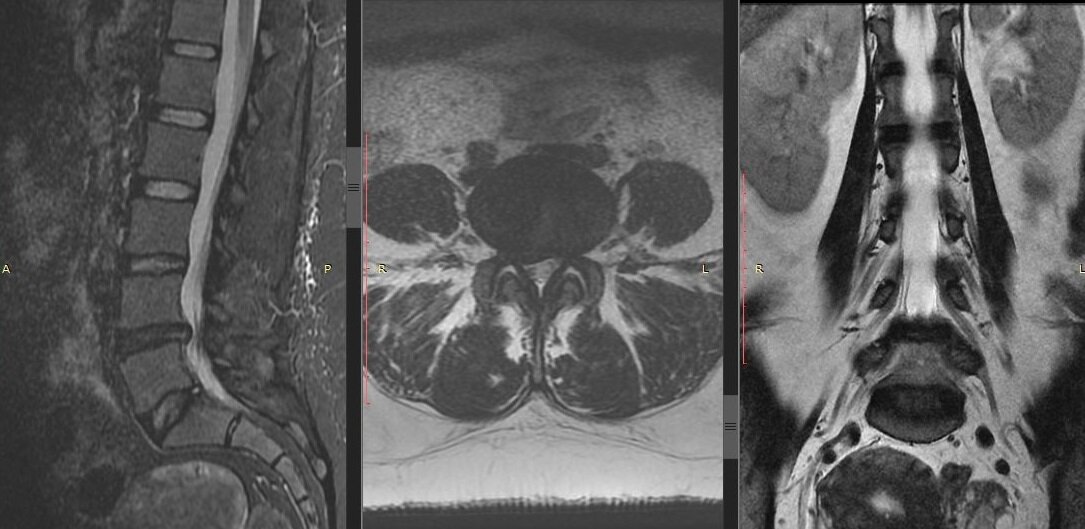

Стоит ли повторять МРТ при грыже поясничного отдела позвоночника?

Картинка с сайта trauma-gvkg.ru